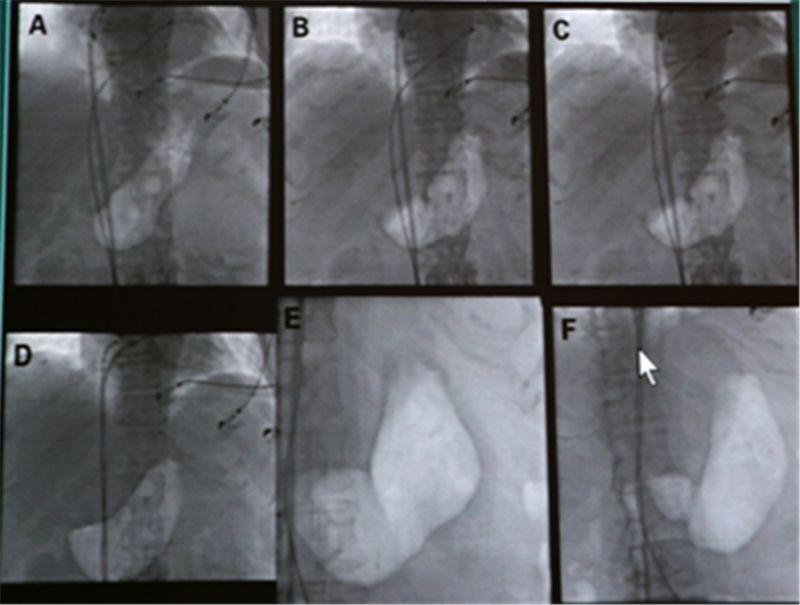

4、手術(shù)治療及新技術(shù):對于嚴重病例,手術(shù)可能是必要的,最新的手術(shù)技術(shù)如內(nèi)鏡引導下胃造瘺等,可以在不切除胃腸道的情況下幫助患者緩解癥狀,干細胞治療和生物反饋治療等新技術(shù)正處于臨床試驗階段,有望為胃癱患者提供更多的治療選擇。